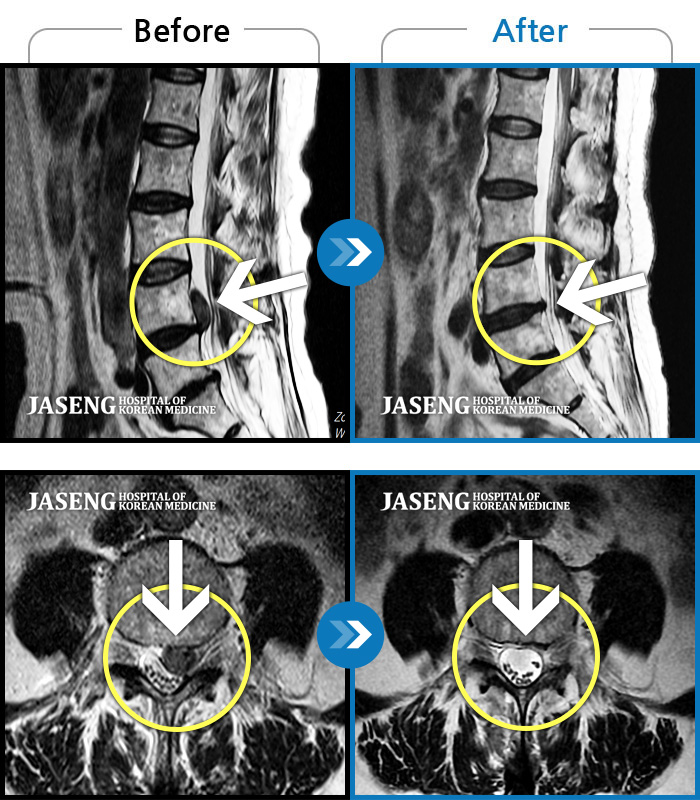

Before

After

환자에게 사전 동의를 받아 동일 조건에서 촬영되었습니다.

개인에 따라 치료 후 부작용이 발생할 수 있으니 의료진과 상담 후 치료를 진행하시기 바랍니다.

우측 허리 뻐근한 통증, 우측 허벅지부터 발목까지 이어지는 당김

좌측 다리 저림 증상이 너무 심하여 앉거나 서는 것이 안되고 다리를 들어올릴 수 가 없었다.